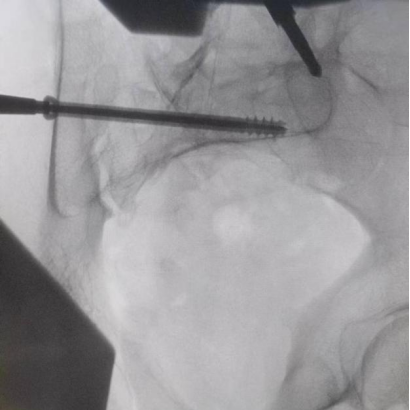

據(jù)了解,患者37歲,為高墜傷患者,入院合并顱腦挫傷、盆腔臟器出血、骨盆骨折多發(fā)傷患者。為最大限度降低手術(shù)風(fēng)險,同時給予患者滿意的手術(shù)療效,術(shù)前綜合評估患者病情,擬定行“天璣機器人”輔助定位下骨盆骨折微創(chuàng)手術(shù)。2月13日10時,手術(shù)正式開始。拉薩市人民醫(yī)院采集患者術(shù)中二維影像,通過骨科手術(shù)機器人擬定螺釘打入位置方向后,吳宏華主任完成手術(shù)設(shè)計,成功為該患者置入了一顆高難度骶髂螺釘,出血5ml,切口1cm。術(shù)后圖像顯示,螺釘位置及方向完全符合手術(shù)規(guī)劃,沒有一絲偏差,手術(shù)最終獲得圓滿成功。

圖為透視下見置入的骶髂螺釘,位置、長度精準,無絲毫偏差